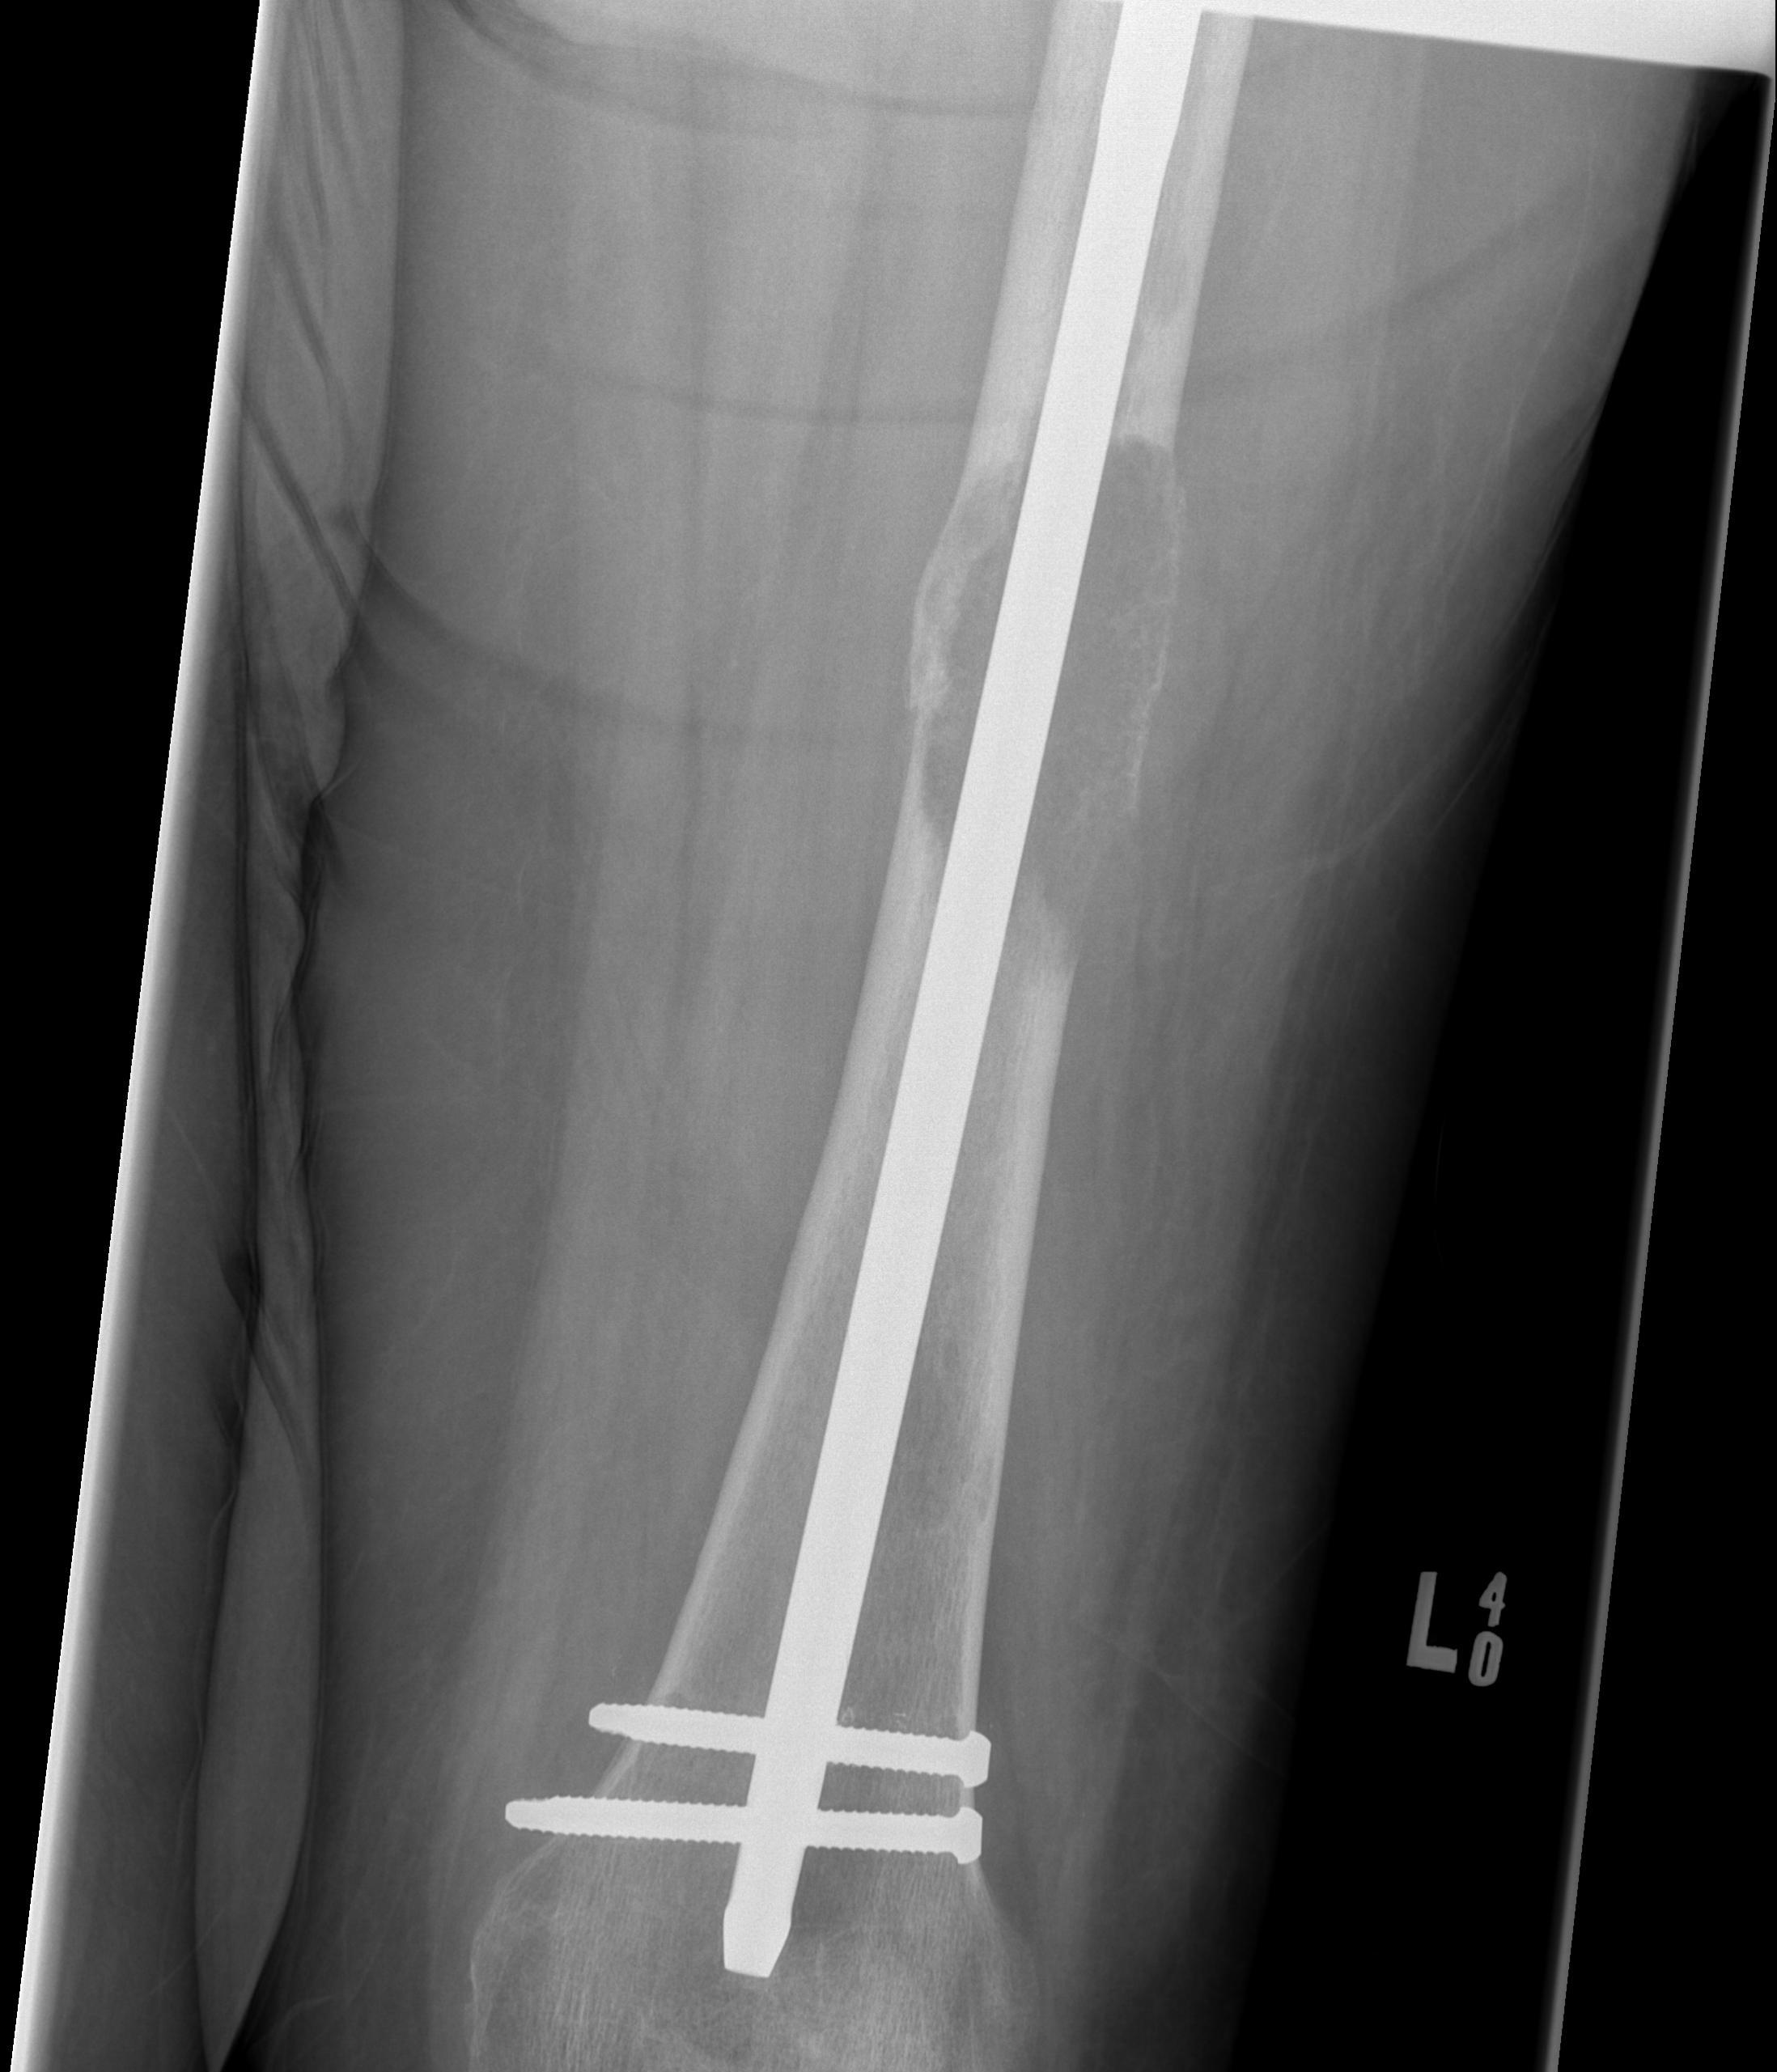

Subtrochanteric / Femoral shaft metastasis

Management

Reconstruction nail

- consider cement

- consider venting

Tibia

Greenbaum et al Am J Orthop 2017

- 43 tibial metastasis

- proximal tibia most common

- variety of treatements

- plate / nail / arthroplasty